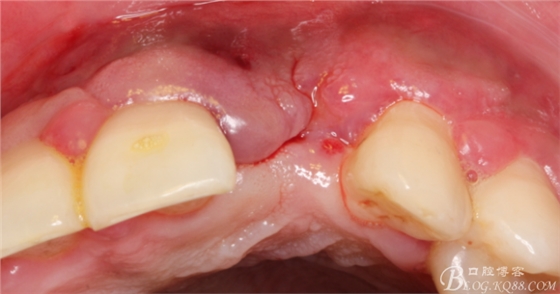

于是我果斷告知患者,手術(shù)失敗了,不能拖延,如不及時(shí)處理,炎癥繼續(xù)發(fā)展會(huì)很快波及鄰牙牙槽骨。患者接受我的建議。切開翻瓣,骨粉及生物膜消失了,骨吸收嚴(yán)重,幸運(yùn)的是,因?yàn)樘幚砑皶r(shí),鄰牙骨支持依然存在。

徹底掻刮。